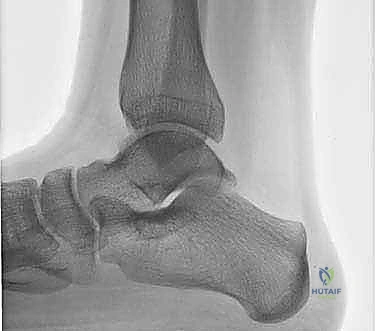

2. التصوير الطبي المتقدم

بما أن الغضاريف لا تظهر بوضوح في الأشعة العادية، يعتمد التشخيص النهائي على تقنيات التصوير المتقدمة:

- الأشعة السينية (X-rays): تُستخدم كخطوة أولى لاستبعاد الكسور العظمية الكبيرة والتهاب المفاصل المتقدم. في بعض الأحيان، يمكن رؤية "ظل" أو كيس عظمي يشير إلى وجود آفة.

- التصوير بالرنين المغناطيسي (MRI): هو المعيار الذهبي (Gold Standard) لتشخيص OLTs. يُظهر الرنين المغناطيسي الغضروف بدقة عالية، ويحدد حجم الآفة، عمقها، وحالة العظم تحت الغضروفي (مثل وجود وذمة عظمية - Bone Marrow Edema).

- الأشعة المقطعية (CT Scan): يطلبها الدكتور هطيف أحياناً للحصول على خريطة ثلاثية الأبعاد دقيقة للعظم، مما يساعد في التخطيط الجراحي وتحديد حجم الرقعة العظمية المطلوبة للزرع.